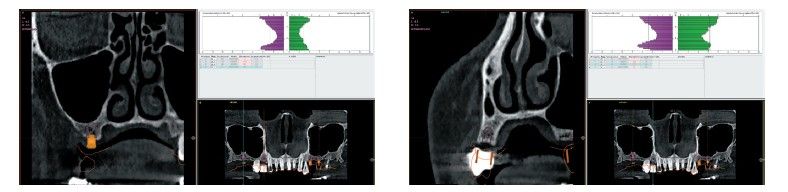

Como primer paso, se realiza un escaneado intraoral de la paciente, para poder generar un encerado virtual con las piezas que queremos rehabilitar con implantes (Figuras 6-8). Esto nos permite planificar con claridad el caso y desde el modelo tridimensional, generar los provisionales y las guías quirúrgicas basadas en la posición protésica, que desde el flujo digital pueden imprimirse (Figuras 9-14). Desde el encerado podemos además generar otras guías, en este caso radiológicas, con las que realizar el Cone-Beam Computed Tomography (CBCT) de planificación. Con esta información tenemos en el mismo estudio radiológico la fusión de nuestra planificación quirúrgica y la posición real de la prótesis adaptada a la oclusión, muy útil para generar una planificación que contempla todos los parámetros. En este caso, se planifican implantes cortos de 6,5 mm en el primer cuadrante, de morfología Core-Xâ, para lograr una correcta estabilidad primaria en un tipo óseo IV como vemos en el corte seccional (Figuras 15 y 16). En el segundo cuadrante, con similares características, planificamos implantes de 6,5 y 5,5 mm de longitud (Figuras 17 y 18).